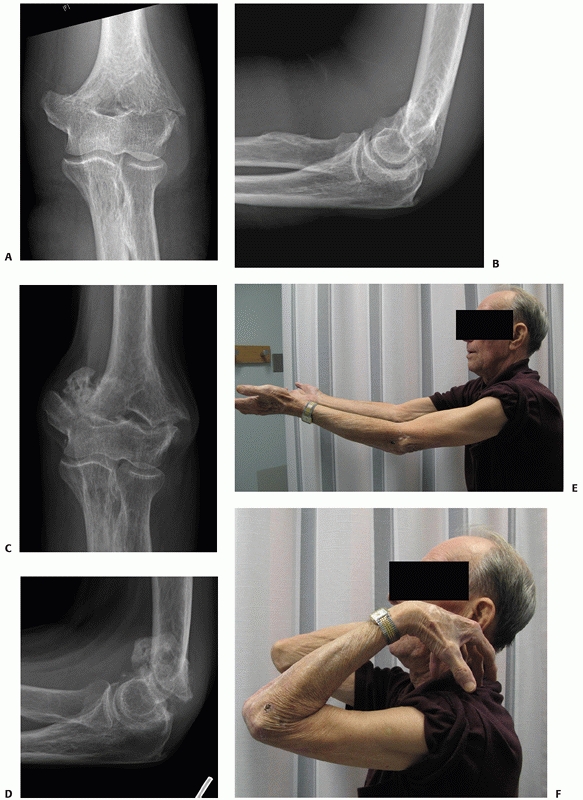

![]() |

FIGURE 33-17

Radiographs of an 88-year-old man with a transcolumn fracture (AO/OTA type A2) deemed medically unfit for surgery because of severe congestive heart failure and inoperable coronary artery disease (A,B). The patient was treated with a collar and cuff and early range of motion. Radiographs at 1-year follow-up (C,D). The patient has no pain with a functional range of motion (E,F). |